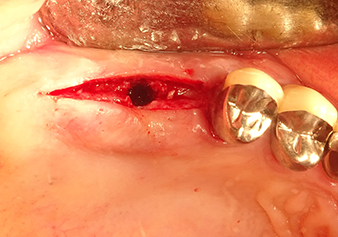

49-летняя пациентка, некурящая и не имеющая ничего примечательного в общей истории болезни, была направлена в нашу хирургическую стоматологическую клинику для хирургического удаления зуба 16 и последующей имплантации. После удаления зуба пациентка перенесла синусит в легкой форме, в результате чего мы сначала выждали шесть месяцев перед проведением операции. Остаточная высота кости при запланированном положении имплантата составляла 3-4 мм (рис. 1 и 2).

После атравматичной подготовки слизисто-костной оболочки, положение импланта было определено с помощью инструмента I1, далее была проведена подготовка поверхности - до тех пор, пока не возникло первичное сопротивление. Пьезохирургические инструменты были использованы в движении вверх и вниз без оказания давления. Пьезоэлектрическая вибрация создавала необходимую кавитацию.

Затем, с помощью инструмента I2A (диаметр 2,0 мм), дно пазухи перфорировалось периодически и в минимально возможном диапазоне. Этот специфический пьезохирургический метод гарантирует, что мембрана Шнейдера не будет повреждена. При использовании Z25P, мембрана уже была слегка приподнята охлаждающей жидкостью, подаваемой через наконечник инструмента (рис. 3). Во избежание высокого давления в ложе имплантата, количество охлаждающей жидкости составляло не более 50%.